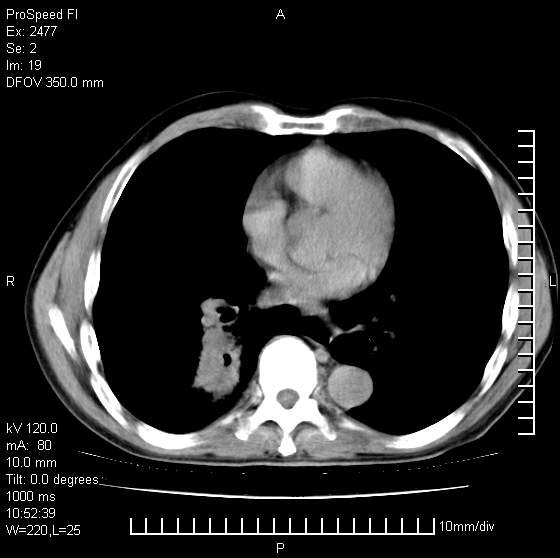

以下是引用天南地北在2007-10-9 14:29:00的发言:[br]1:右上肺结核[br]2:右肺下叶肿块:不支持肺癌,首先考虑炎性病变-肺脓疡可能性大[br]理由:1:临床病史支持,肺脓肿症状不明显应该是不规则服药造成。[br] 2:肿块边缘模糊,周围可见炎性渗出,长毛刺,内见支气管征,不过有点不规则。[br] 我感觉下肺癌这个诊断有点偏左,建议积极抗炎治疗后复查

以下是引用卜一在2007-10-9 15:55:00的发言:[br][br] [br] 1:右上肺结核[br]2:右肺下叶肿块:不支持肺癌,首先考虑炎性病变-肺脓疡可能性大[br]理由:1:临床病史支持,肺脓肿症状不明显应该是不规则服药造成。[br] 2:肿块边缘模糊,周围可见炎性渗出,长毛刺,内见空气支气管征,不过有点不规则。[br] 我感觉下肺癌这个诊断有点偏左,建议积极抗炎治疗后复查![br]支持! [br] [br] [br]

以下是引用wxy7406在2007-10-9 21:02:00的发言:[br]结合临床病史首先考虑感染性病变,但周围型肺癌不能除外,1.患者年龄偏大2.临床有咯血3.(也觉得是最重要的一点)病灶内有偏心性空洞。

以下是引用王仕学在2007-10-9 13:48:00的发言:[br]右下肺周围性肺癌可能性大,最好活检吧

以下是引用hhcckk在2007-10-9 15:18:00的发言:[br]右上肺病灶考虑结核,病灶多种形态并存(纤维化、增殖性病灶并存)[br]右下肺病灶比较难说,个人意见更趋向于“天南地北”的诊断----肺脓肿[br]1、病人有明显的寒战,高热,肿瘤病人很少出现[br]2、病灶周围的肺纹理走向柔和,没有肿瘤病灶常见的集束征[br]3、病灶边缘的毛刺较长,恶性肿瘤多为短毛刺[br]痰中血丝和病人的年龄是两个不利于良性肿块的因素,建议早点活检

以下是引用ydx_74在2007-10-9 15:53:00的发言:[br]右上肺结核,右下中心性肺癌可能大,肺门淋巴结肿大。